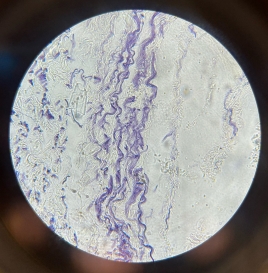

Mucous Tissue